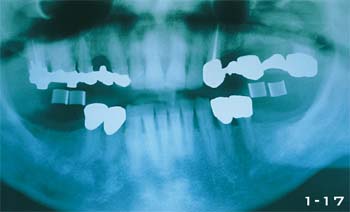

Abb. 1-17 Panoramaaufnahme eines 55-jährigen Mannes, dessen abnehmbare Prothese durch eine festsitzende Versorgung abgelöst werden sollte. Der Behandlungsplan sah vier osseointegrierte schraubenförmige Implantate im Unterkiefer sowie Sinuslift und zylindrische Implantate im Oberkiefer vor.

Abb. 1-18 Röntgenstatus nach Abschluss der Behandlung mit einem zufrieden stellenden Ergebnis.